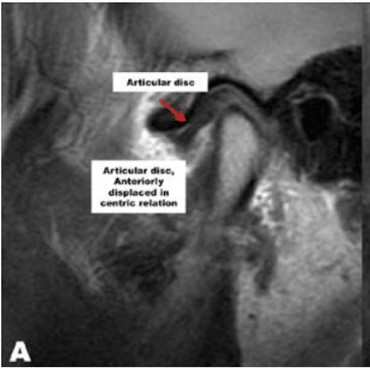

Тут мыщелок в норме (Фото от Larry M.Wolford, DMD)

...а тут диск смещён вперёд (по-научному это называется «вентральная дислокация диска»)